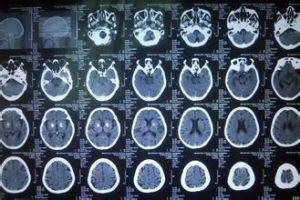

(一)肌萎縮側索硬化(amyotrophiclateralsclerosis)早期一側上肢運端肌肉萎縮,逐漸出現其它肢體肌萎縮,下肢及軀幹偶可受累,最後面肌及舌肌受累才出現萎縮,1-2年才發展到全身肌萎縮。早期錐體束損害不明顯,故早期診斷較困難,必須有明確的錐體束徵才可確診。約半數以上有Babinski征,無感覺障礙及大小便失禁,發生褥瘡者罕見,早期有蟻行感、疼痛等。(二)腦出血(cerebralhaemorrhage)多有高血壓病史,常在50~60歲發病,體力活動或情緒激動時突然起病,發展迅速,早期有頭痛、嘔吐等顱內壓增高徵象,意識障礙,伴有腦膜刺激征及偏癱、

右側巴彬斯基征陽性失語等腦局部症狀,病情加重可出現昏迷,四肢肌張力低,鼻聲呼吸,反覆嘔吐,常有雙側瞳孔不等大,一般為出血側瞳孔擴大,部分病例兩眼向出血側凝視,出血灶的對側偏癱,肌張力偏低,巴彬斯基征陽性。針刺癱瘓側無反應。腰穿可呈血性腦脊液,CT顯示高密度灶。MRI、T1W、T2W腦內高信號區。(三)腦血栓形成(cerebralthrombosis)多發於60歲以上老年人,伴有高血壓病史及腦動脈硬化者和冠心病或糖尿病史,男性多於女性。常於睡眠中或安靜休息時發病,1-4天內達高峰、昏迷較輕,頭痛、嘔吐者少見,瞳孔無變化,眼底動脈硬化,病灶對側肢體癱瘓,常出現偏癱、失語、偏身感覺障礙、偏盲等。頸部有抵抗,肌張力低,病側巴彬斯基征、卡道克征及高爾登征陽性。腦脊液檢查多正常,顱腦CT顯示低密度區。MRI、T1M低信號區,T2M稍高信號區。(四)多發性硬化(multiplesclerosis)多在20-40歲之間發病,很少在10歲以下(3%)及50歲以上(5%)發病者,女性多於男性。多有緩解與復發病史,多有復視,單側或雙側肢體無力,肢體的感覺異常,錐體束受損可出現痙攣性肢體癱,可表現為截癱、四肢癱三肢癱、偏癱或單癱,腱反射亢進,Babinski征陽性。(五)良性流行性神經肌無力(benignepidmicneuralmyasthenia)初期可有低熱或無發熱,潛伏期約1周左右,伴有上呼吸道感染,咽痛、胃腸道症狀等。全身淋巴結腫大,以頸部淋巴結腫大明顯,神經系統受累者側出現頭痛、頸硬及頸痛、肌肉痛。眼球震顫,復視,肌陣攣,咽喉部肌無力,肢體軟弱乏力,腱反射正常、亢進或減退,病理征陽性。肌束顫動,伴有肌肉疼痛及壓痛,皮膚感覺過敏。失眠及多夢、情緒不穩、注意力不集中,憂鬱、癔病樣發作等。(六)高血壓腦病(hypertensiverencephalopathy)多見於急進型或嚴重緩進型高血壓病人,表現為劇烈的頭痛、頭暈、嘔吐、頭脹或精神錯亂。本病的全面發展可能需要12~48小時,以後出現全身性抽搐,肌陣攣,昏迷及局灶性神經障礙,並可出現半身輕癱、失語、局灶性癲癇發作以及視網膜性或皮質性失明,也可出現視乳頭水腫,視網膜出血及滲出,血壓突然升高。病理反射陽性。腰穿腦脊液多正常,壓力增高。(七)多發性腦梗塞痴呆(dementiacausedmultiplecerebralinfarcion)主要症狀有記憶力減退,智力遲鈍,定向力障礙,判斷力差及缺乏自知力。近記憶明顯減退,容易遺忘,但遠記憶一般保持較好,對很熟的人不認識,把時間地點弄錯。專業知識也遺忘,計算力差,說話詞不達意,甚至不連貫,精神淡漠,反應遲鈍、自私自利,自我中心,伴有情緒不穩定,脾氣急躁,多疑,妄想等。晚期有痴呆,橈動脈、足背動脈、股動脈兩側搏動正常,可聽到血管雜音。腱反射增高,雙側Babinski征陽性。掌頦反射、吸吮反射、眉間反射陽性。 (八)葡萄膜大腦炎(uveoencephalitis)發病年齡以25-50歲多見,常於春天發病。先有腦膜刺激症狀、嗜睡、意識障礙,偶可有偏癱和失語。偏癱側肌張力增高,腱反射增強,巴彬斯基征陽性。發病1-2周出現急性瀰漫性葡萄膜炎,視力驟減,睫狀體充血,虹膜後粘連,瞳孔縮小,玻璃體混濁,或視網膜浮腫。視乳頭充血,邊緣不清,甚至視網膜剝離。尚可出現耳鳴、耳聾和平衡障礙。可出現皮膚白斑、白髮和脫髮等。(九)肝性脊髓病(hepaticmyelopathy)本病實際上並不少見,因多數病人肝性腦病並存,臨床症狀被腦病的意識及運動障礙所掩蓋而誤診。病理檢查發現脊髓後束、側束的脫髓鞘改變。此病發病緩慢,進行性加重,雙下肢無力、走路不穩,可伴有括約肌障礙。雙下肢肌力,減退、肌張力增高,腱反射亢進常有陣攣,病理反射陽性。音叉震動及關節位置覺減退,痛、觸覺正常。癱瘓肢體肌力3-4級。完全性截癱少見,無明顯的病損感覺水平。血氨升高。(十)亞急性聯合變性(subacutecombineddegeneration)本病無明顯的家族史或性別差異。多在中年慢性起病,漸進性加重,早期足趾及手指末端對稱性感覺異常,漸向近端伸延。兩下肢無力,肌張力減低,輕度肌萎縮,腱反射遲鈍。深淺感覺均可出現障礙,呈周圍性分布,可伴有肌肉壓痛,後索與側索變性時有四肢無力、肌張力增強、腹壁反射消失。巴彬斯基征、卡道克征陽性。並有大小便失禁、可伴有惡性貧血的蒼白,消化不良及舌炎。周圍血象及骨髓塗片可見巨細胞性高血紅蛋白性貧血。(十一)甲狀旁腺機能亢進(hyperparathyroidism)主要症狀有舌肌震顫,舌肌萎縮,類似肌萎縮側索硬化症。有的可有聲音嘶啞,聲帶麻痹,吞咽困難。少數病人合併有神經性耳聾或腱反射亢進,叩一側腱反射時對側肢體亦出現反射活躍,巴彬斯基征陽性。下肢近端的肌肉常易疲勞和無力。骨盆帶及肩胛帶的肌肉在活動後常有疼痛及感覺異常,並可出現肌萎縮。受侵肌肉的肌張力低,腱反射活躍。背部疼痛,並伴有壓痛,無固定部位。(十二)癔病性截癱(hystericparaplegia)女性多見,病前多有精神因素,弛緩性與痙攣性截癱均可見,變化多端,瞬間呈弛緩性,瞬間又呈痙攣性,沒有括約肌障礙,無褥瘡及皮膚營養障礙與肌萎縮,肌腱反射與淺反射正常。絕無Babinski征。富於暗示性。